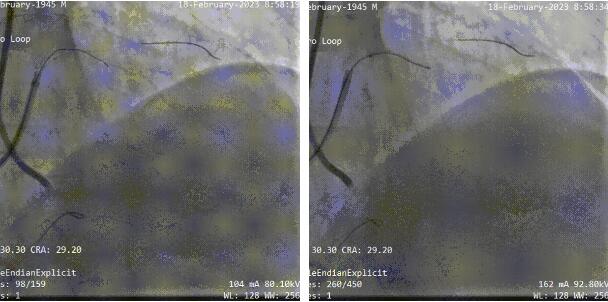

此次患者入院准备再次PCI,开通前降支CTO,该CTO闭塞段长,入口及走形不清晰,对此,周浩教授与中国医学科学院阜外医院尹栋教授讨论后,决定在新型的3D打印技术的指导下行CTO-PCI术。3D重建打印后能提供比冠脉CTA更清晰的判断信息包括闭塞段入口、血管走形、钙化分布以及血管直径等。

术前使用了马克医疗提供的3D打印技术,其提供的三维重建数字影像和3D打印模型能清晰的指出CTO闭塞段情况包括入口钙化分布等情况的:

依据3D打印指导+双侧造影,双腔微导管+UB3导丝一刻钟的时间左右成功通过CTO段到远端真腔:

术后最终结果: